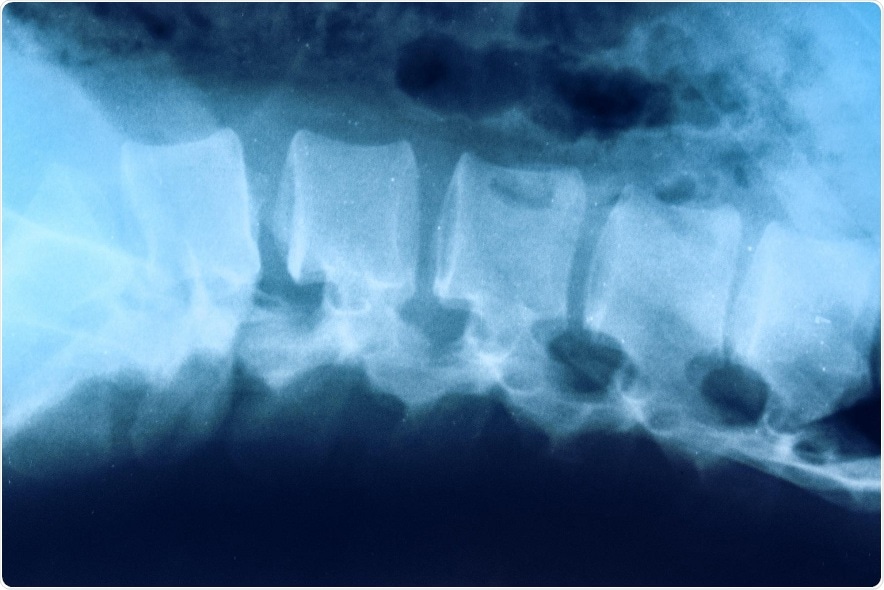

Shining light on spinal cord injury

The researchers aim to understand what happens after spinal cord injury at the level of individual cells. They’ll do this using a new probe developed by Ravichandran that causes dying cells to glow under the microscope. He and Kipnis will be able to track the dead cells as they are swallowed up by immune cells, called phagocytes, that remove them from the body.

This will provide important insights into how the body responds to spinal cord injury. For example, the researchers will seek to determine if neurons are dying because immune cells called microglia aren’t up to the task of removing harmful debris. Or if other immune cells, called macrophages, can’t get to where they’re needed.

By determining what types of cells are involved in the injury response, and exactly what those cells are doing, the researchers will identify potential avenues to improve the treatment of spinal cord injuries.